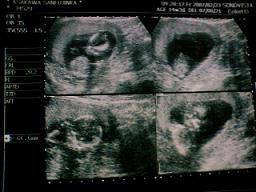

2007年2月23日撮影。

14w4d

この日から産科扱いになり、頭殿長は測らないようになりました。

代わりにBPD(頭の直径)を測って成長をみるらしい。

そしてBPDは28.2oで、週数相当のようです。

4分割の左上が全体写真で顔が写ってます。手はガッツポーズしてるみたいw

右上は羊水量。右下は顔のアップ写真だよ。(心霊写真みたい、って思っちゃった^^;ごめん★

左下の写真でBPDを測りましたw

右の写真は先生が「もう頭殿長は測らないよ〜」といいながら測ってくれた写真ですw

一応測ってもらった頭殿長は68.6o・・・前回より縮んでるっ!

ま、まぁ今回初ビデオ録画をしてもらったんだけど、だいぶ動いていたからきっとそのせい(・∀・)